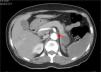

CTA of the abdomen/pelvis (Figure 4) at patient discharge: Abdominal aortic lumen patent throughout its trajectory, without identifiable thrombus. The ischemic clinical presentations described in the previous CT scan are identified, with better pancreatic ischemic lesion definition.

The patient was treated with systemic anticoagulation therapy and the identified remaining aortic thrombus resolved (Figure 4). When she was transferred back to her local hospital, we recommended long-term anticoagulation with Coumadin derivatives, target INR of 2.5–3.5, and aggressive control of risk factors: glycemic and blood pressure control, together with discontinuation of oral contraception. Vaccination prophylaxis due to functional asplenia was recommended. Gynecologic examination and further investigation of the anemia was also recommended. Although we initially admitted the microcytic hypochromic anemia could be due to iron deficiency related to menorrhagia, normal ferritin and low transferrin did not indicate sideropenia. Moreover, such a low MCV with a normal red blood cell count could indicate thalassemia trait, a relatively common condition in the patient's geographic origin. RDW did not distinguish iron deficiency from minor thalassemia.31